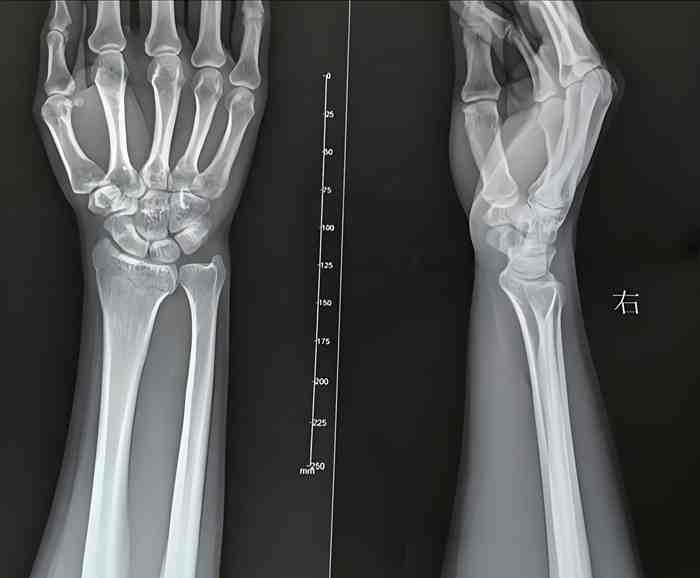

一晚,原告工作时摔倒受伤,凌晨前往医院就诊,诊断为右侧桡骨骨折,周围软组织稍肿胀。同日,原告将CT片等就诊资料发给被告业务经理,业务经理通过微信向原告转账支付了医药费。原告申请工伤未果,向法院提出诉讼请求,要求确认原被告之间存在劳动关系。被告则认为双方并不构成劳动法意义上的劳动关系,仅为“灵活用工”,垫付医药费也仅仅是基于人道主义。